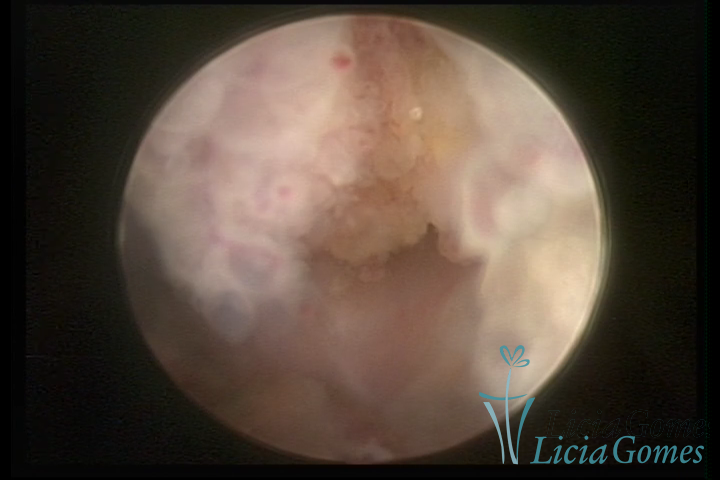

A histeroscopia permite analisar as características da superfície endometrial, não podendo avaliar a profundidade ou o grau de invasão miometrial.

Mas poderá verificar se as lesões são do tipo: focal; regional ou difusa

Salientando que cabe à microscopia (Histopatológico), o diagnóstico diferencial da Hiperplasia com atípias e o Adenocarcinoma de endométrio ou outro tipo de neoplasia endometrial.

Este pode apresentar uma gama variável de aspectos macroscópicos, com aspecto pseudopolipoide; lembrando tecido cerebroide ou com reação deciduoide;a vascularização superficial é mais evidente e com vasos em formatos de saca-rolha ou espirais visualizando também a vascularização com atípias, com aumento do calibre dos vasos superficiais, pode ser encontrado também tecido em necrose, poderá haver um pequenos dendritos (papilomatoso).